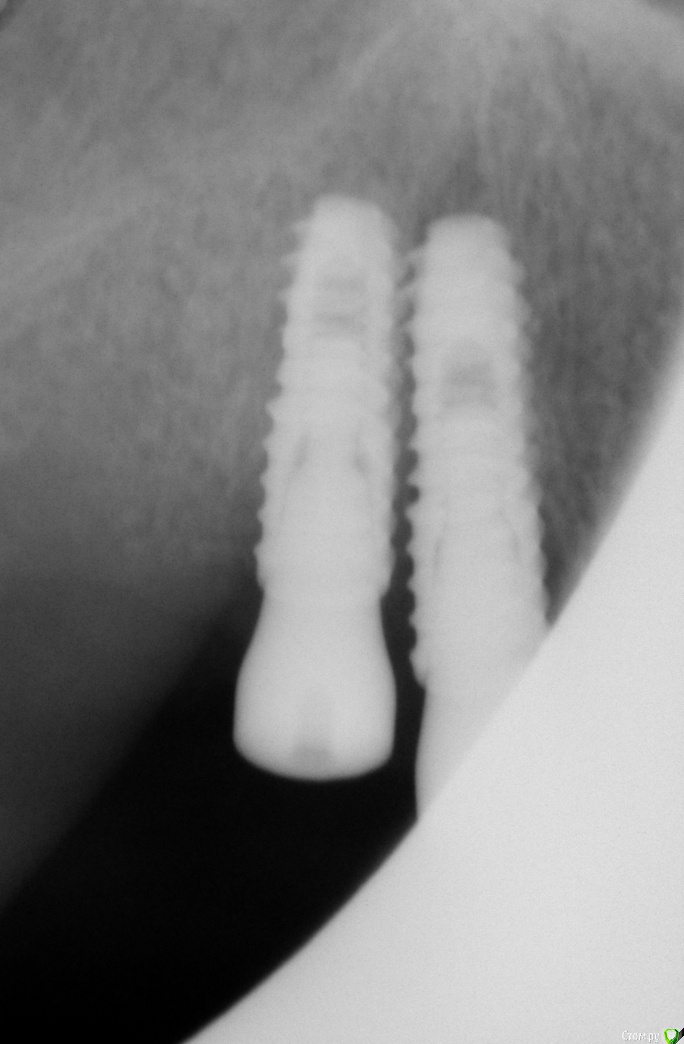

Bier Опубликовано 23 января, 2020 Поделиться Опубликовано 23 января, 2020 возможно конечно снимок искажает так, но если во рту 2 имплантата справа стоят так же близко друг к другу, они оба на удаление. Ссылка на комментарий

ALLA0105 Опубликовано 24 января, 2020 Автор Поделиться Опубликовано 24 января, 2020 Чисто визуально расстояние между имплантами больше 3 мм. Ссылка на комментарий

red_butler Опубликовано 24 января, 2020 Поделиться Опубликовано 24 января, 2020 Чисто визуально расстояние между имплантами больше 3 мм.Нужно сделать прицельный rg на визиографе Ссылка на комментарий

ALLA0105 Опубликовано 28 января, 2020 Автор Поделиться Опубликовано 28 января, 2020 Явно расстояние меньше 3 мм. Прошу вас подскажите, что необходимо предпринять, чтобы исправить ситуацию. Буду благодарна за консультацию. Ссылка на комментарий

red_butler Опубликовано 28 января, 2020 Поделиться Опубликовано 28 января, 2020 Явно расстояние меньше 3 мм. Прошу вас подскажите, что необходимо предпринять, чтобы исправить ситуацию. Буду благодарна за консультацию.Удалять Ссылка на комментарий

Bier Опубликовано 28 января, 2020 Поделиться Опубликовано 28 января, 2020 Явно расстояние меньше 3 мм. Прошу вас подскажите, что необходимо предпринять, чтобы исправить ситуацию. Буду благодарна за консультацию.попробовать удалить тот, что ближе к центру. Переставить его. Но так близко оставлять нельзя. Отсроченные проблемы неизбежны. 1 Ссылка на комментарий